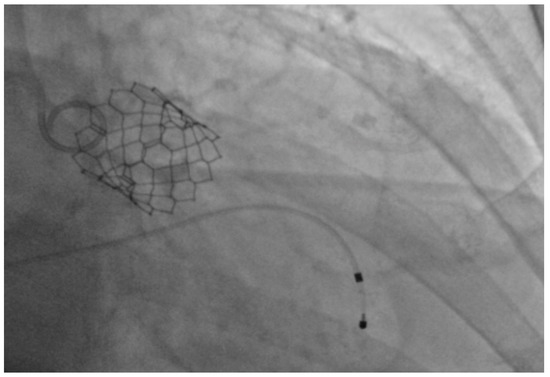

Figure 2.

Expanded SAPIEN S3 valve within the native aortic valve.

Under general anesthesia, the right and left femoral arteries were each accessed with 6-french sheaths. A temporary pacemaker was placed in the right ventricle through an 8-french sheath in the right femoral vein. Balloon valvuloplasty was performed by advancing a balloon via the right femoral artery sheath, and during rapid ventricular pacing at 160 beats per minute, inflating it across the aortic valve to clear the stenosis and to deploy the 26-mm SAPIEN S3 bioprosthetic aortic valve (Figure 1), which expanded within the native aortic valve (Figure 2). The purpose of rapid ventricular pacing during TAVI is to reduce cardiac output, which facilitates balloon inflation across the valve and placement of the bioprosthetic aortic valve. The mean valvular gradient after TAVI decreased to 1.9 mm Hg (normal is <5 mm Hg). There were no intraoperative complications. The patient was extubated and transferred to the coronary care unit with the temporary transvenous pacemaker, which was removed two days later.